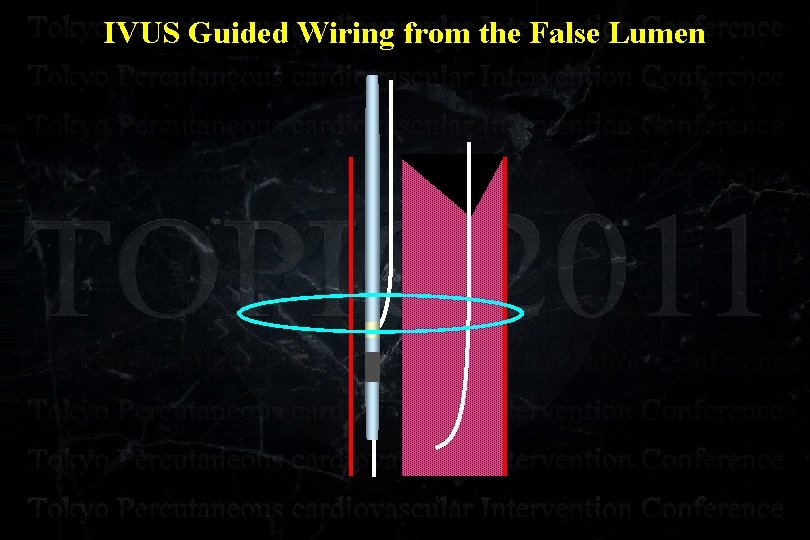

IVUS Guided Wiring from the False Lumen